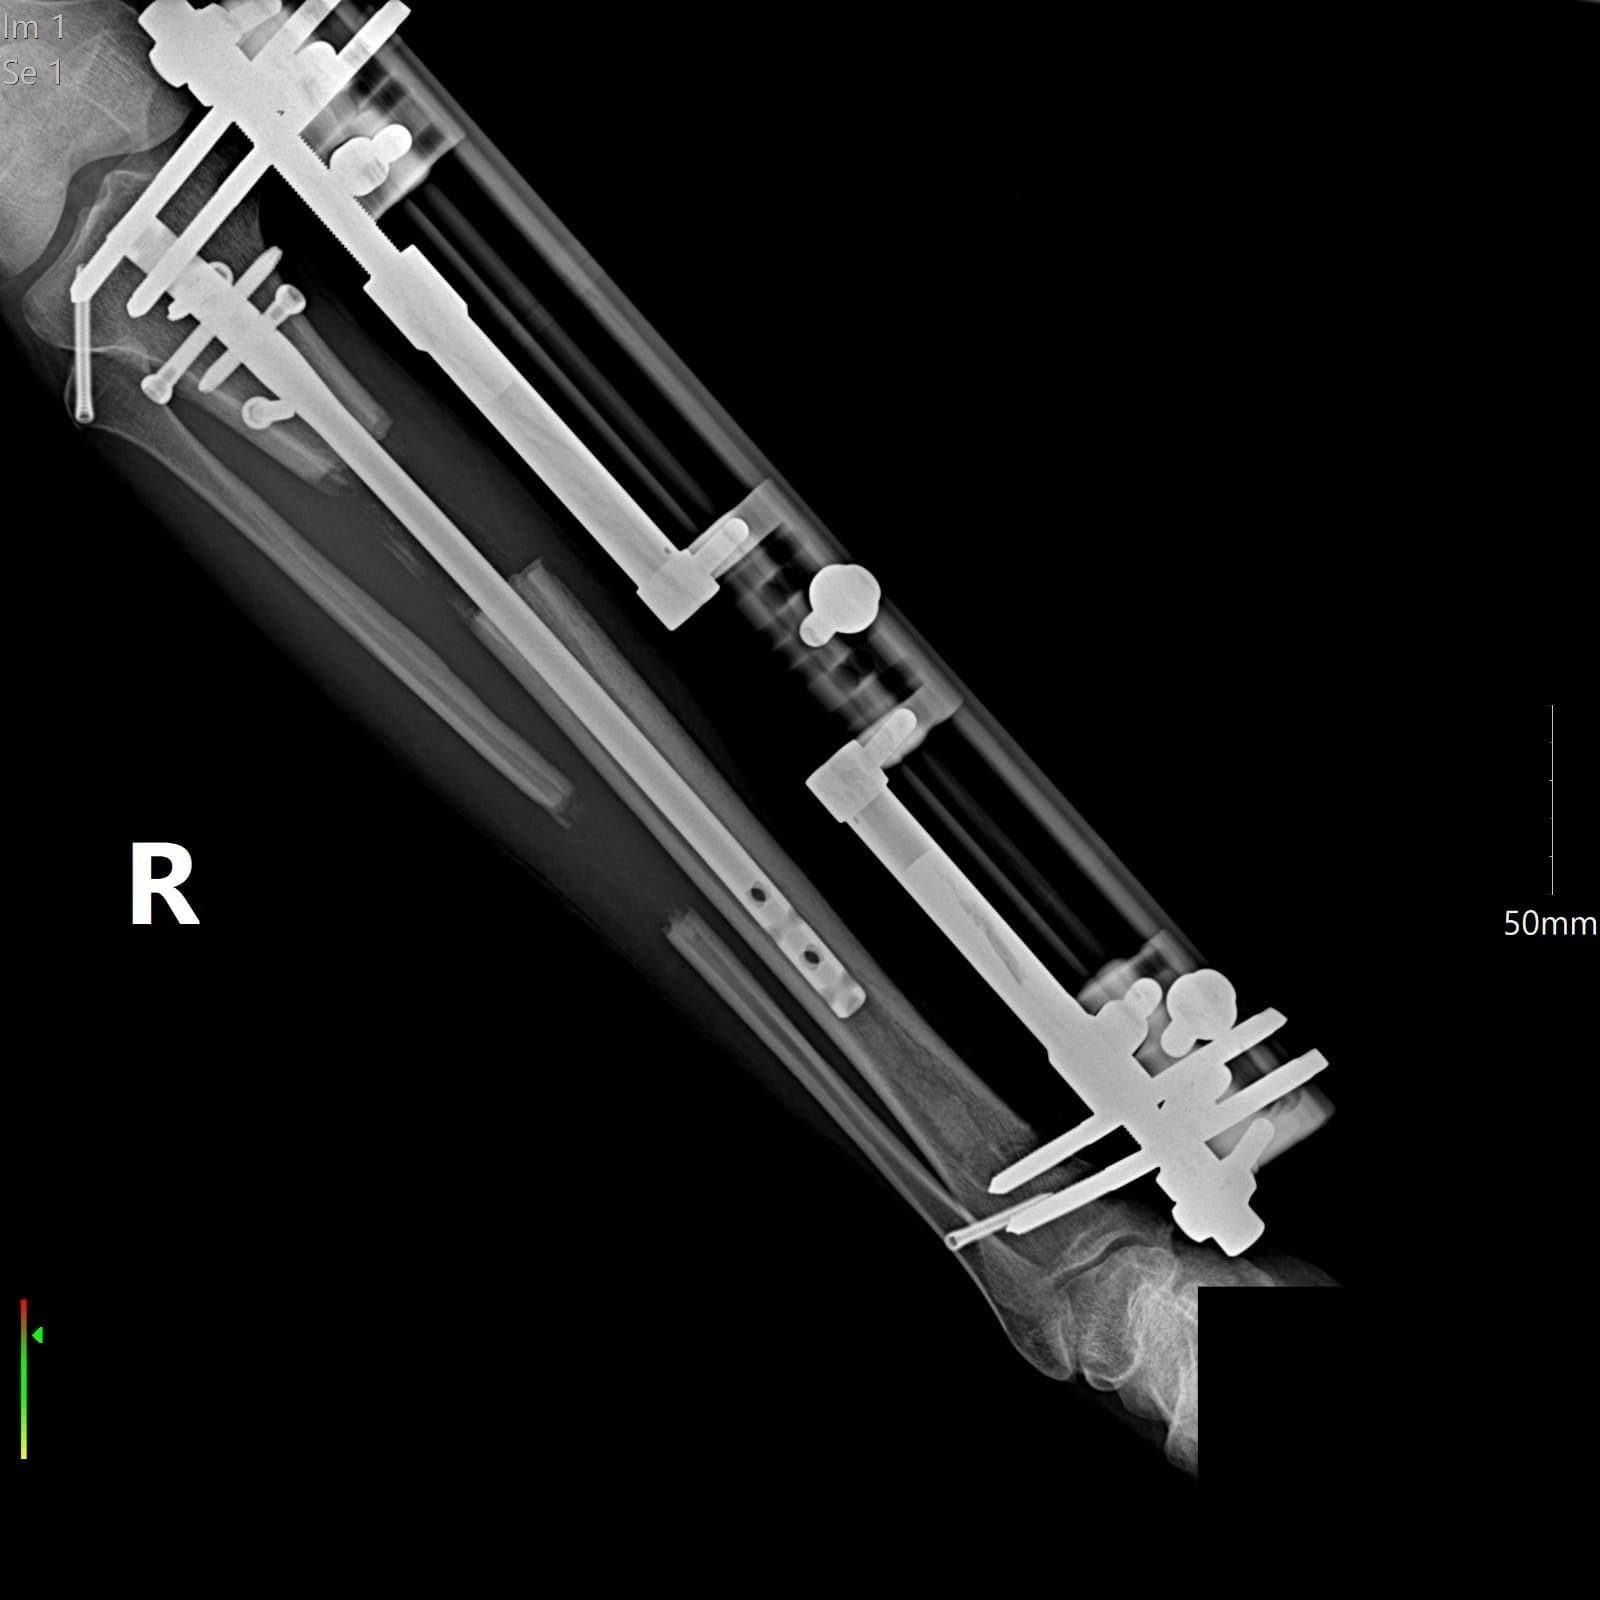

Lengthening Over a Nail (LON) is relatively new technique that combines external fixator distraction osteosynthesis with the convenience of intramedullary nail.

The LON method (lengthening over nails), also known as external fixator combined with intramedullary nail, is a holding system attached by the skin. This method is used for broken bones and lengthening surgery. The extension is done with external fixators, the patient extends with a special screw every day by 1 mm to – 1.5 mm every 6 hours (4×6 hours), with the screw on the outside of the external fixator by 0.25 mm – to 0.5 mm, so that at the end of the day 1 to 1.5 mm can be reached.

The external fixator is attached to the bone through the skin in LON method surgery. The intramedullary nail (intramedullary screws) is inserted on the femur either through a small skin incision above the hip or below the kneecap. To extend the lower leg, the intramedullary nail is also inserted below the kneecap.

With the external fixator, the thigh and lower leg bones are gently lengthened. The surgery lasts on average between 3 to 5 hours under general anesthesia.

The LON method (Lengthening Over Nail) is a well-established approach used in limb lengthening procedures. It combines the use of internal and external fixation devices to support bone lengthening in a controlled and safe way. A metal rod (intramedullary nail) is inserted into the bone, while an external fixator is applied to the outside of the limb. Together, they ensure the bone stays aligned and stable throughout the treatment.

Nails and external fixators are key components in the LON method. The internal nail provides strength and structure from within the bone, while the external fixator guides the gradual lengthening and keeps the limb secure during the process.